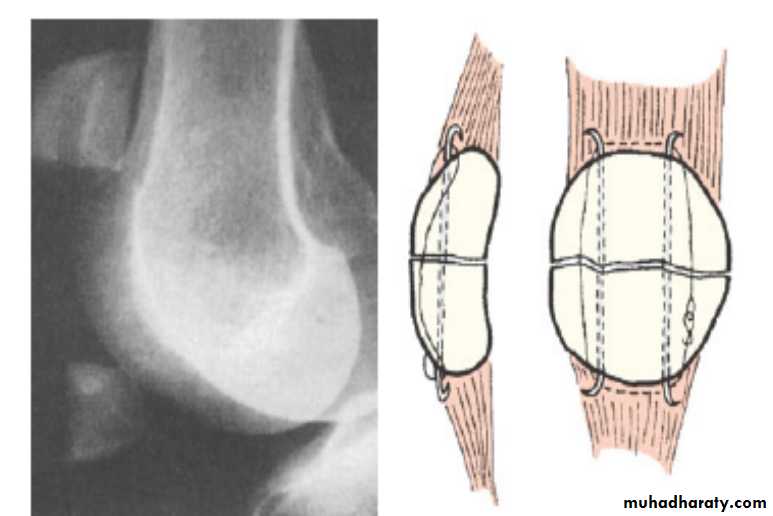

Fractures of patella

it can be caused either by:

A- direct force :lead to undisplaced crack or comminuted fracture and here the extensor expansion usually remain intact (the patient can elevate straight leg).

B- indirect force :

lead to transverse fracture with gap between the fragments Caused by resisted extension

( sudden contraction of the quadriceps muscle against resistant ).

Associated with tears of collateral extensor expansions and failure of extensor mechanism (patient cannot elevate leg straight).

Treatment :

For the fractures caused by direct force :

In undisplaced or minimally displaced fractures

The treatment is by p.o.p cylinder holding the knee straight should be applied for 3–4 weeks.

during this time quadriceps exercises are to be practised, haemoarthrosis should be aspirated. Severely comminuted and

displaced fracture

treated by

internal fixation or delayed patellectomy.

Internal fixation

Indirect force:

Operation is essential.

Through a longitudinal incision the fracture is exposed and the patella repaired by the tension-band principle .

The tears in the extensor expansions are then repaired.